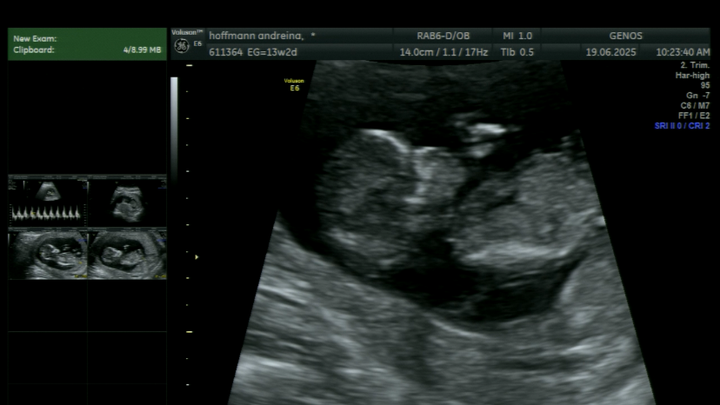

Hace poco me confirmaron que mi bebé, Constanza, tiene síndrome de Turner, una condición genética poco común que implica varios desafíos en su desarrollo. Además, se le detectó un higroma quístico y un derrame pleural, lo que complica aún más su situación y requiere controles médicos constantes y atención especializada.

Los médicos me aconsejaron interrumpir el embarazo… pero no pude hacerlo. En cada ecografía su corazoncito seguía latiendo con fuerza, y ahí entendí que ella está luchando por vivir. Yo tampoco me voy a rendir. Decidí seguir adelante, confiando en Dios, en la medicina y en el profundo amor que siento por ella.

Recently, I found out that my baby, Constanza, has Turner syndrome, a rare genetic condition that comes with several developmental challenges. She was also diagnosed with a cystic hygroma and pleural effusion, which further complicate her condition and require constant medical care and close monitoring.

Doctors advised me to terminate the pregnancy… but I couldn’t do it. At every ultrasound, her little heart was still beating strong, and I realized that she’s fighting to live. So I decided to fight with her. I chose to continue this journey with faith in God, in medicine, and in the deep love I already feel for her.